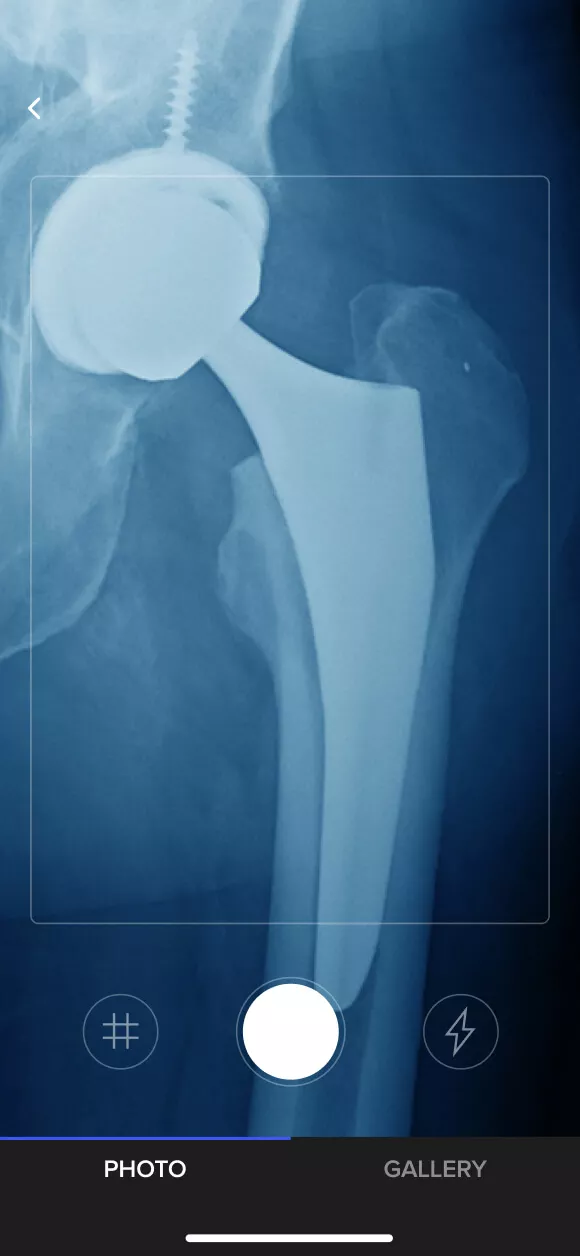

The app prompts doctors to take a photo of a prosthetic’s X-ray using a smartphone.

The image is run through an artificial neural network, cross-referencing the photo against a crowd-sourced database of implant silhouettes.

Once the implant is identified by the machine learning models, cases are evaluated by verified surgical team members.